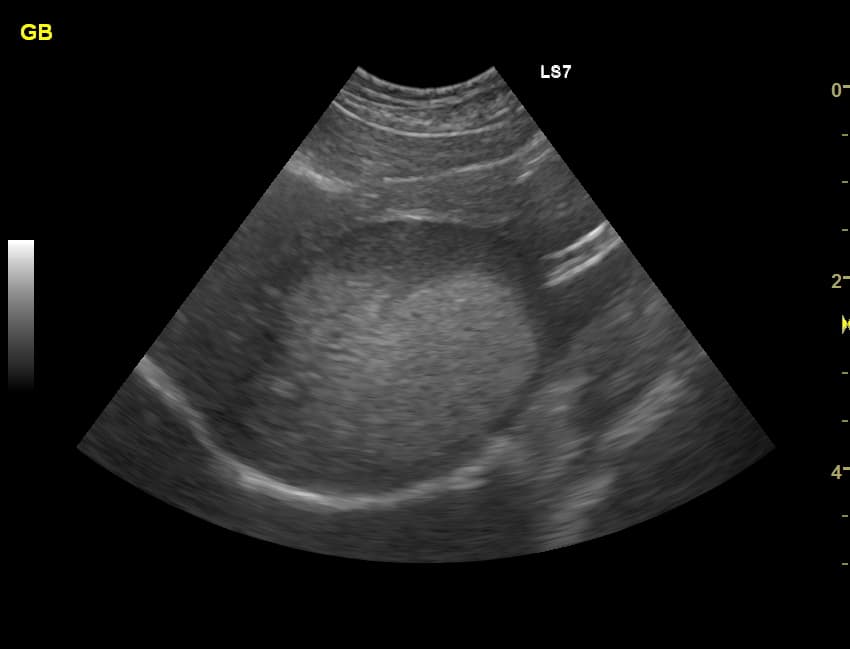

胆泥症(たんでいしょう)は、胆嚢内にどっろとしたの胆汁成分がたまる状態です。

エコー検査で確認でき、多くの犬によくあり、症状がないことがほとんどです。

諸検査で、胆泥症だけ、ということがよくあります。健康ドッグや他の疾患を疑う場合の検査で、偶然に見つかることが多いです。

今日の咳の原因究明のため検査でも見つかりました。犬の10頭に1〜2頭は胆泥症があると聞いたことがあります。